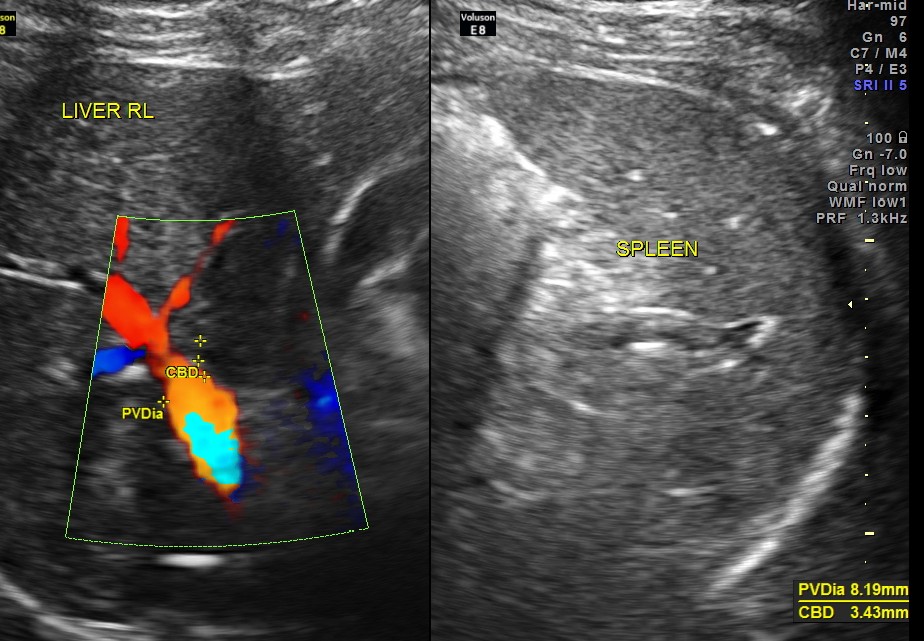

An ultrasound abdomen was done as part of evaluation of anemia.

Now for the unexpected findings . To finish off the scan , I was sweeping the aorta, IVC and the pre and post aortic regions.

The following image was obtained with the transducer in the mid epigastric region and an inch to the left of the mid line.

This mass visualised there . This was antero-lateral to the aorta and showed mixed echotexture , with some vascularity.

This was not mobile and all i could offer was a description of what was seen with the impression of a mass of unknown origin – ?? enlarged node and advised further work up.